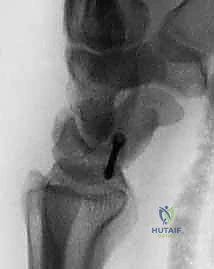

Radiographic evaluation is mandatory prior to surgical intervention. Anteroposterior, lateral, and open-mouth odontoid radiographs of the cervical spine must be obtained to definitively exclude congenital cervical spine anomalies or atlantoaxial instability. In atypical presentations (e.g., presence of neurological deficits, torticollis presenting after 6 months of age without a history of pseudotumor, or severe pain), magnetic resonance imaging (MRI) of the brain and cervical spine is indicated to rule out central nervous system pathology.

Clinical & Radiographic Imaging